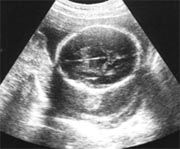

胎児の大きさ(妊娠27週末)☆身長/約38cm ☆体重/約1200g